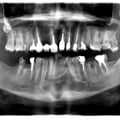

Жертва, або студентів, або інтернів, або не кваліфікованих стоматологів. Результат - нераціональне зубне протезування при генералізованому пародонтиті, виведення пломбувального матеріалу за межі кореня в гайморову порожнину